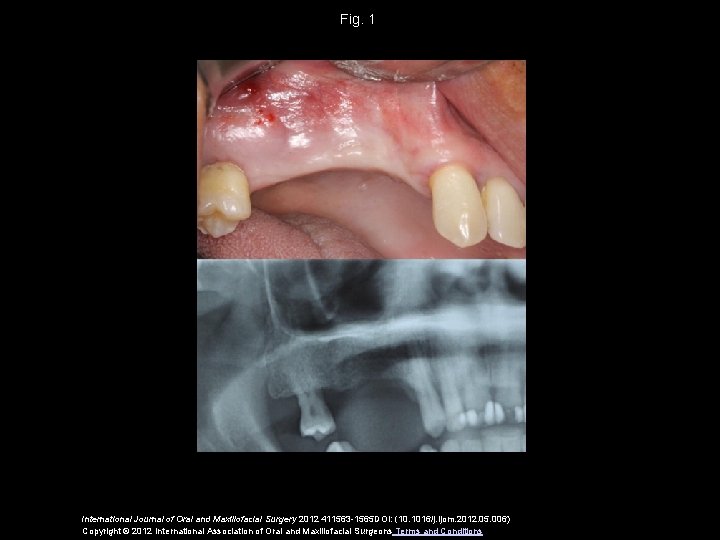

Fig. 1 International Journal of Oral and Maxillofacial Surgery 2012 411563 -1565 DOI: (10. 1016/j. ijom. 2012. 05. 006) Copyright © 2012 International Association of Oral and Maxillofacial Surgeons Terms and Conditions